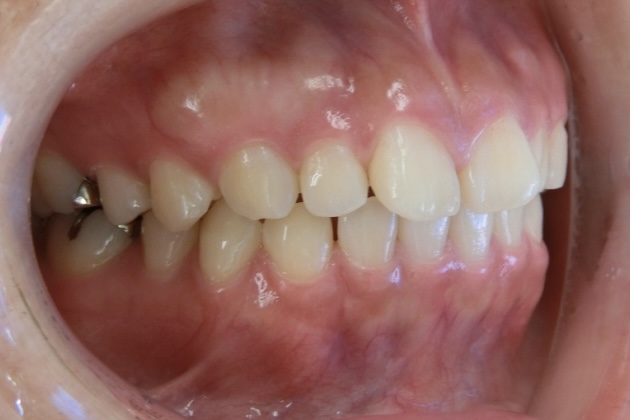

BEFORE

20代女性 すきっ歯が気になる

20代女性の患者さまで、4人のお子さまを育てながら、できるだけ目立たない方法ですきっ歯を治したいとご相談に来院されました。子育てや日常生活への影響をできる限り抑えながら治療を進めたいというご希望を踏まえ、当院で専門的に行っているマウスピース矯正にて治療を進めました。